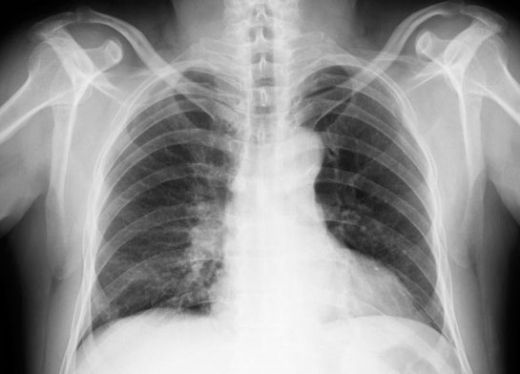

Akciğer kanseri, dünya genelinde en yaygın ve ölümcül kanser türlerinden biridir. Hastalık ilerledikçe metastaz belirtileri ortaya çıkabilir. Bu yazıda, akciğer kanseri metastazının belirtileri, yayılma alanları ve tedavi yöntemleri hakkında bilgi verilmektedir. Erken tanı ve düzenli kontrollerin önemi vurgulanmaktadır.

Sonuç Akciğer kanseri metastazı, hastalığın ilerlemesiyle birlikte önemli sağlık sorunlarına yol açabilir. Belirtilerin farkında olmak ve erken tanı için düzenli kontroller yaptırmak, tedavi şansını artırmaktadır. Tedavi seçenekleri hastanın durumu ve metastazın yayılım alanına göre değişiklik göstermektedir. Her hastanın durumu benzersizdir ve tedavi planı, uzman hekimler tarafından bireysel olarak belirlenmelidir. Ekstra Bilgiler Bu makale, akciğer kanseri metastaz belirtileri ve tedavisi hakkında genel bir bakış sunmakta olup, her bireyin durumu için özel bir tedavi planı oluşturulması gerektiğini vurgulamaktadır. |